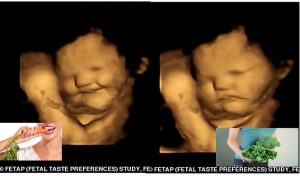

Hatred of green vegetables begins in the WOMB! 4D ultrasound scans reveal babies smile when their mum eats carrots –